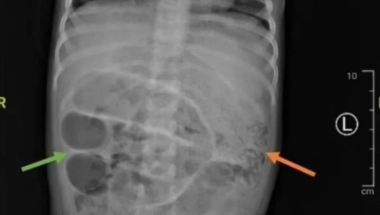

Tokom operacije, lekari su identifikovali i uklonili brojne crve Ascaris lumbricoides , dugačke nekoliko centimetara, koji su stvorili "gužvu" u tankom crevu deteta.

- Rez napravljen za uklanjanje parazita napravljen je na tački otprilike 50 centimetara od debelog creva. Crvi su poslati na dalju analizu u laboratoriju. Istovremeno, analize krvi su pokazale da dete boluje i od anemije, česte pojave u ovakvim slučajevima. Paraziti apsorbuju značajan deo gvožđa i drugih hranljivih materija u telu, uzrokujući, između ostalog, probleme u razvoju deteta. Mladom pacijentu je određena terapija antibioticima, hidratantnim rastvorima i preparatima protiv crevnih parazita. Otpušten je nedelju dana kasnije - prenose mediji.